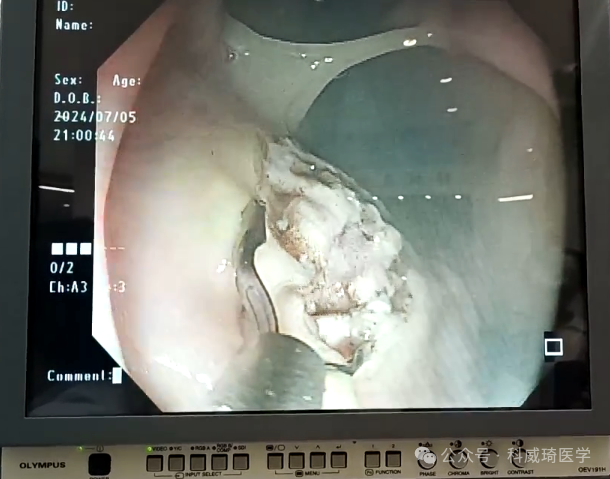

本次科威琦医学ESD专场将为大家带来,内镜黏膜下剥离术(ESD)的最新进展、操作技巧及临床应用。

现场ESD手术实操过程中,将实际展示通过[科威琦医学]活检钳带刻度功能,成功解决了[内镜下病理结构大小体内影像取证]。